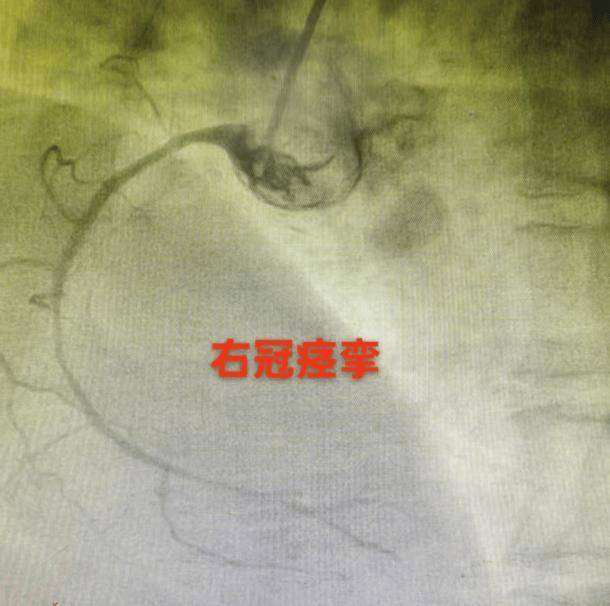

另一位40多岁的男性患者,有抽烟习惯,每日一包,平时应酬多,生活作息极不规律。春节期间,他连续多日熬夜。正月初十的清晨六点,起床后突发剧烈胸痛,被紧急送至广东省中医院大学城医院。造影显示冠状动脉三支血管严重痉挛,右冠远端重度狭窄,姚耿圳副主任医师仔细甄别,行冠脉内推注硝酸甘油并行腔内影像学检查后,避免了一次不必要的支架植入。